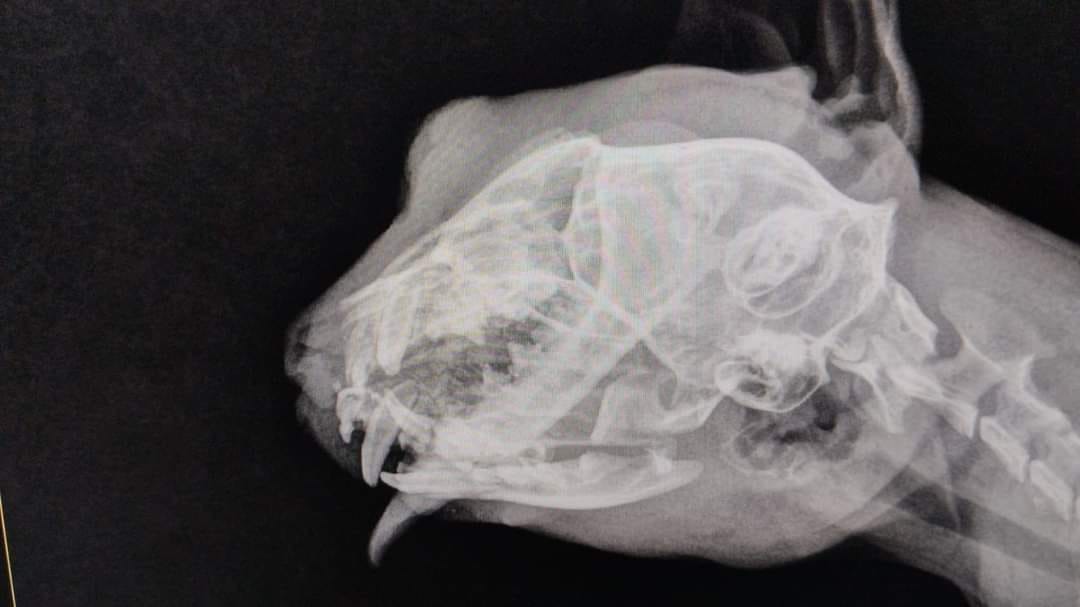

En este sentido, el gatito cuenta con fractura en ambos maxilares, tiene el paladar partido por dentro en 2 fracciones, lo que le genera problemas con la respiración, pues la lesión llegó hasta los conductos nasales por lo que será sometido a cirugía.